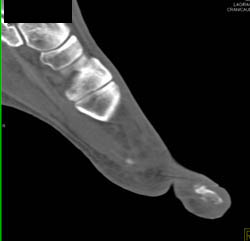

Ct Knee Without Vascular Injury